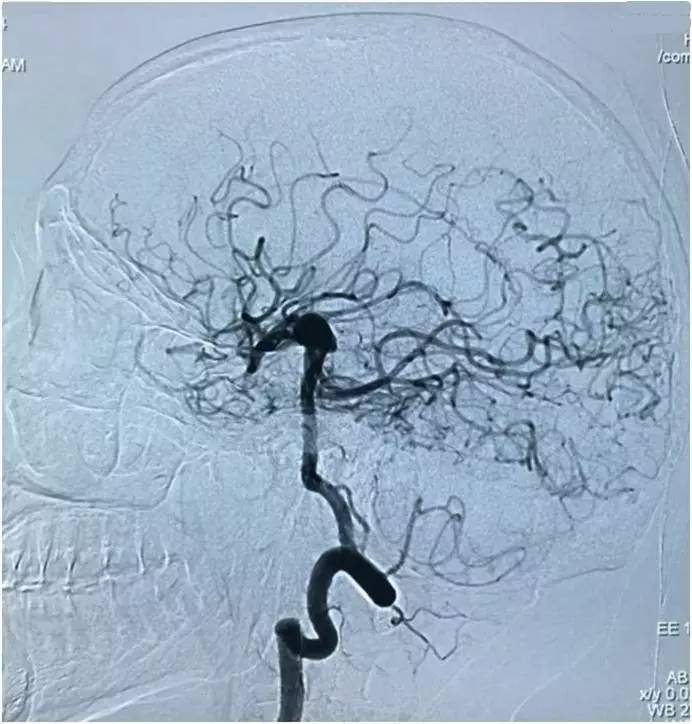

以下图像为DSA,显示基底动脉顶端动脉瘤,左侧小脑上动脉瘤,左侧PCA P1段微小动脉瘤,双侧颈内动脉眼动脉以远闭塞,前循环靠后循环通过后交通动脉代偿。

▼左颈总动脉造影正位

▼右颈总动脉造影正位

▼左椎动脉造影正位

▼左椎动脉造影侧位